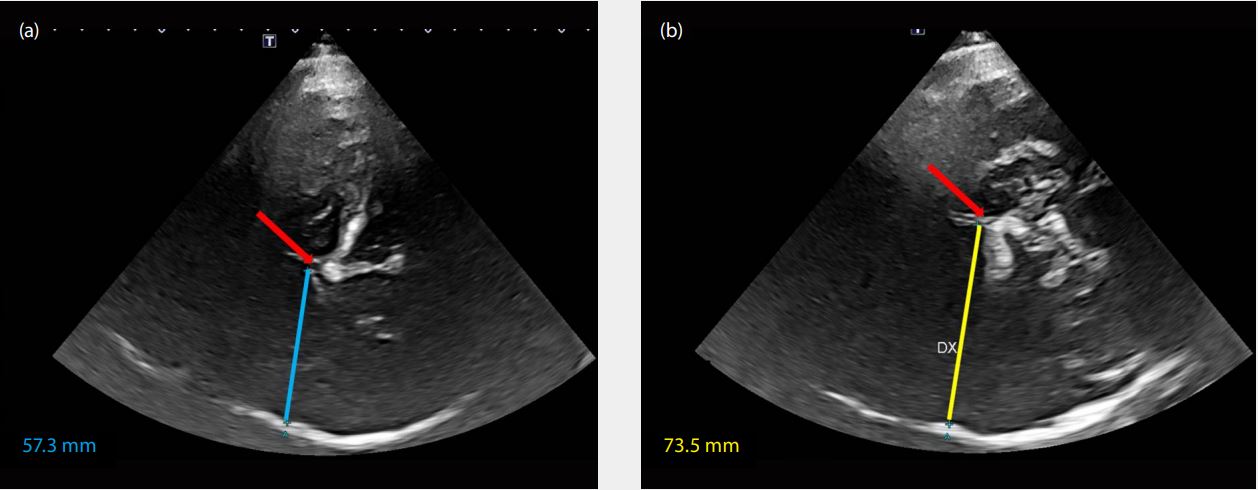

(a) Сонографія через праве скроневе вікно для вимірювання лівої півкулі.

(b) Сонографія через ліве скроневе вікно для вимірювання правої півкулі.

Середня лінія і зміщення середньої лінії

Методика оцінки третього шлуночка дуже легка і швидка. Отримані висновки можна використовувати як у гострій фазі, так і під час моніторингу у неврологічних ситуаціях, де має місце гіпертензія, як у випадку, представленому тут.

Зміщення середньої лінії (ЗСЛ) = (A-B)/2

Ця швидка техніка також дуже застосовна для пацієнтів, які перенесли краніектомію, і особливо під час спостереження за ними в відділеннях інтенсивної терапії.